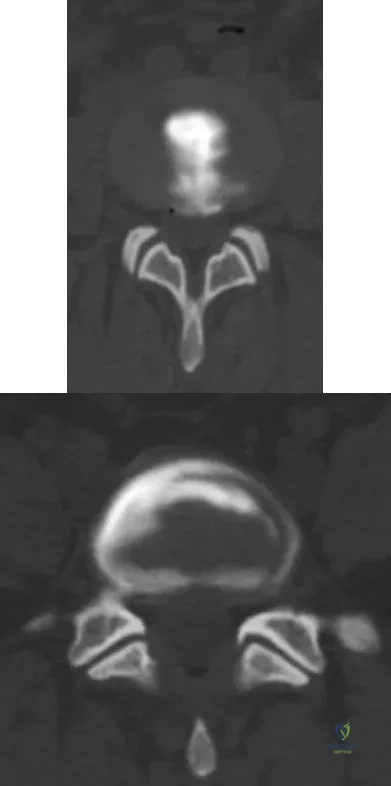

Figures 28a and 28b show the sagittal and axial lumbar MRI scans of a 72-year-old man who reports dull aching back pain that spreads to his legs, calves, and buttocks. He has had the pain for several years and it is precipitated by standing and walking and relieved by sitting. His symptoms have been worsening over the past year and he notes that he is leaning forward while walking to help relieve his symptoms. He has had no treatment to date. What is his prognosis if he chooses to pursue nonsurgical management for this condition?

Explanation